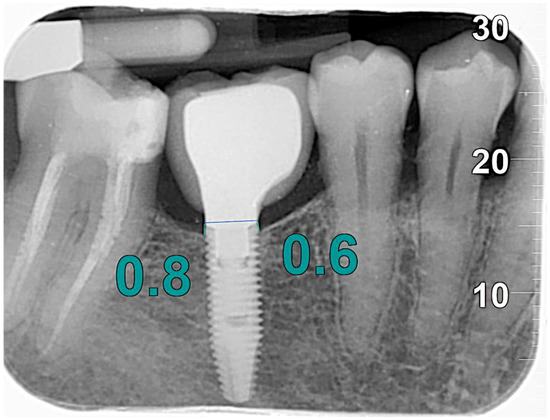

Measurements were made by comparing the changes in marginal bone height over time. The bone level was determined by taking the most coronal portion of the implant fixture and the contact point between the implant and the marginal bone ridge as reference points. To standardize the analysis, a virtual reference line tangent to the shoulder of the implant was considered, from which a line parallel to the long axis of the fixture was drawn to the most coronal point where the bone came into contact with the implant, both mesially and distally (Figure 1).

Figure 1. MBL measurements.